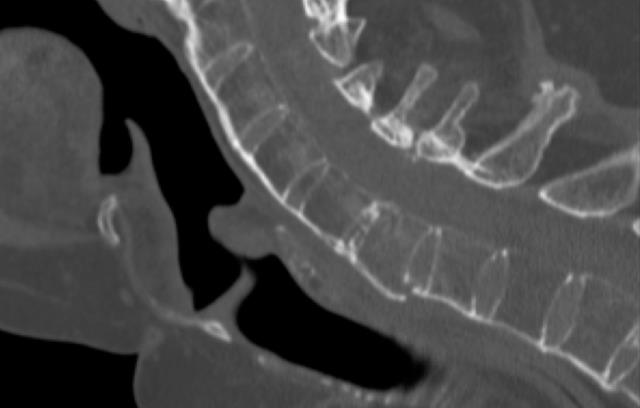

Se trata de un proceso inflamatorio que afecta a las inserciones tendinosas y de los ligamentos de las articulaciones, preferentemente del esqueleto axial, comenzando generalmente por las articulaciones sacroilíacas, pero que afecta a toda la columna, especialmente en las uniones discovertebrales.

A consecuencia de estos brotes inflamatorios se produce la fijación de las articulaciones, quedando toda la columna vertebral transformada en un bloque único, con ensanchamientos a nivel de los discos, lo que le da un aspecto parecido a una caña de bambú.